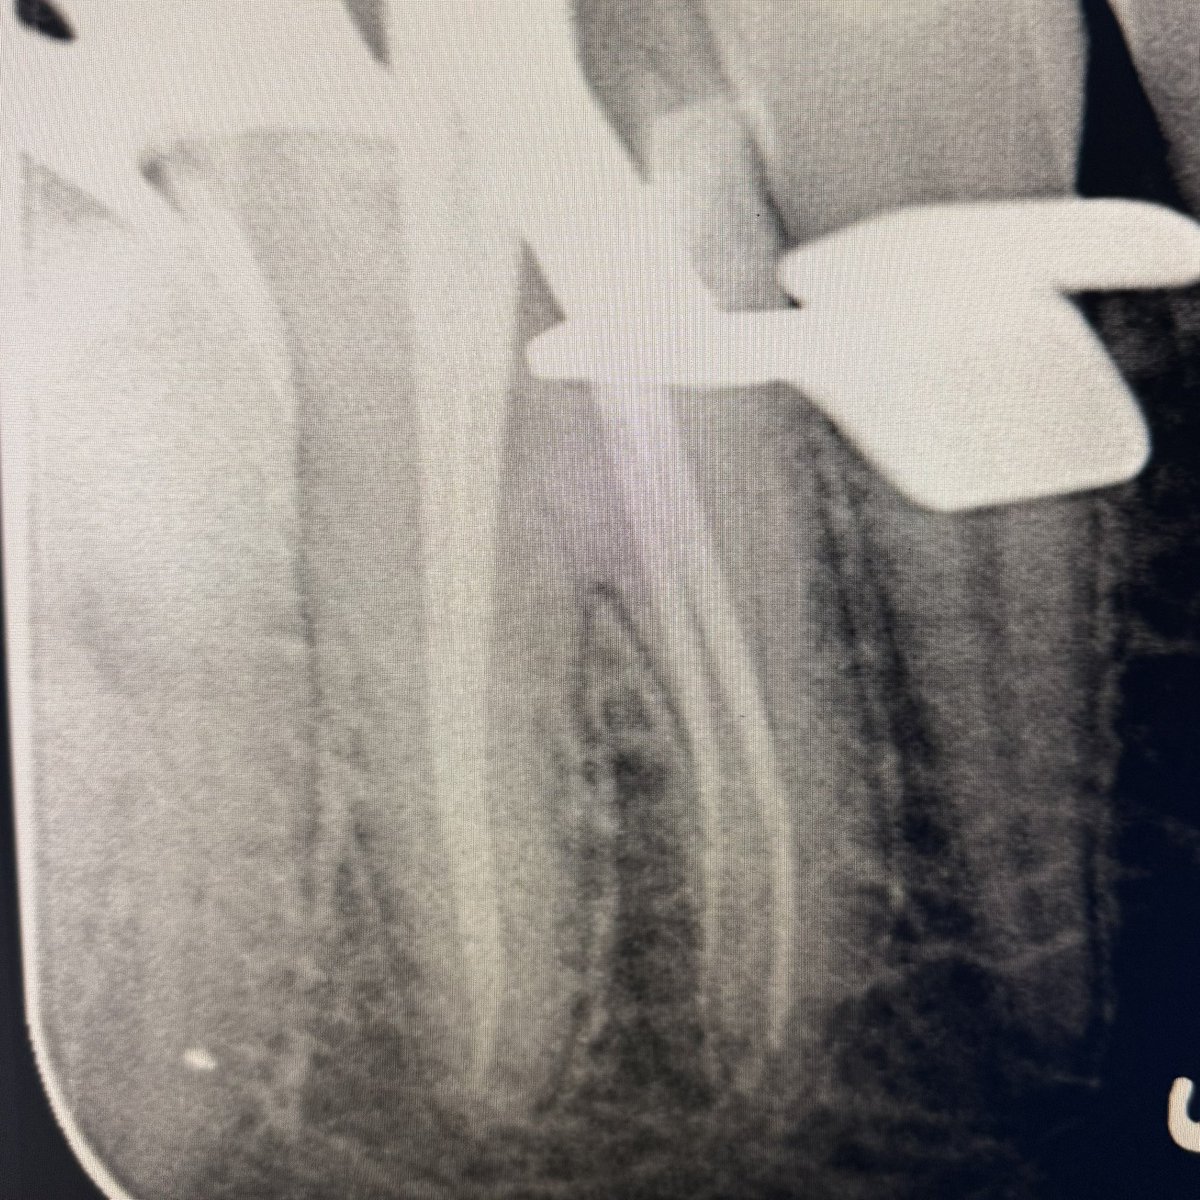

Today’s case:

Rct of #11 Dx : PI/AAA

• 1st visit: Open access, irrigation, abscess drainage, and dressing the canal with Ca(OH)₂.

• 2nd visit (after 30 days): Reopening the tooth, irrigation performed; the canal was completely dry and ready for obturation.

Patient is fine😁

English